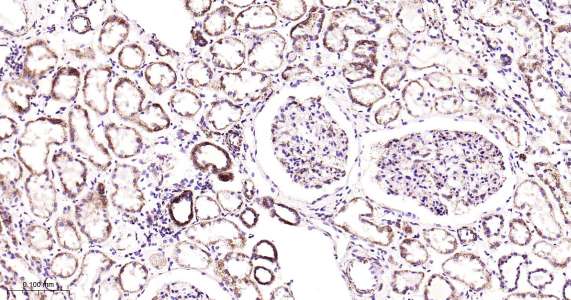

Immunohistochemical analysis of paraffin embedded human kidney tissue slide using IHC0443H (Human MtTF1 IHC Kit).